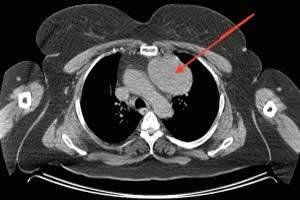

Timusda kütlənin olub olmadaığını dəqiqləşdirmək üçün KT və ya MRT lazımdır (Şəkil 26,27).

Şəkil 26. KT. Timoma

Şəkil 27. KT. Timoma